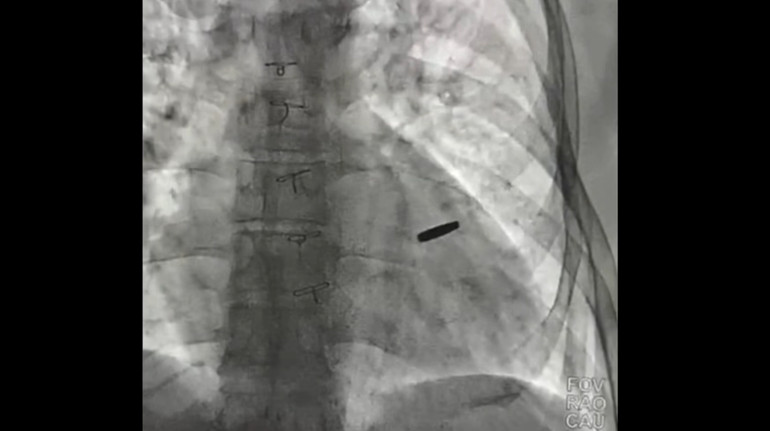

"Ми зробили рентген і всі необхідні обстеження, дивилися, чи не пошкоджені коронарні судини та легені. Виявилося, що куля стирчить у серцевому м’язі і обросла судинною оболонкою.

Її вдалося локалізувати за допомогою спеціального магніту, який ми використовуємо для пошуку уламків чи куль у м’яких тканинах, бо іноді важко знайти дрібні металеві частинки в серці чи м’язах", – сказав Тодуров.

За його словами, лікарі оперували на працюючому серці – під час хірургічного втручання його не зупиняли. Після того, як кулю видалили, кардіохірурги зашили невеликий отвір і зупинили кровотечу. Операція пройшла успішно, без значної втрати крові та ускладнень.